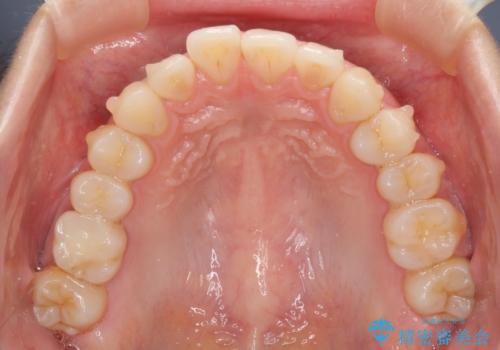

- 上下前歯のデコボコを気にして来院された患者様です。

インビザラインによる上下歯列の側方拡大と後方移動、IPR(歯と歯の間を削る)にるスペースの獲得により歯列を整えることとしました。

1日22時間の装着時間をしっかり守ってくださったので、予定していた1年よりも早く治療を終えることができました。

インビザライン矯正特有の奥歯がしっかりと咬合しない感覚も改善され、大変満足していただきました。